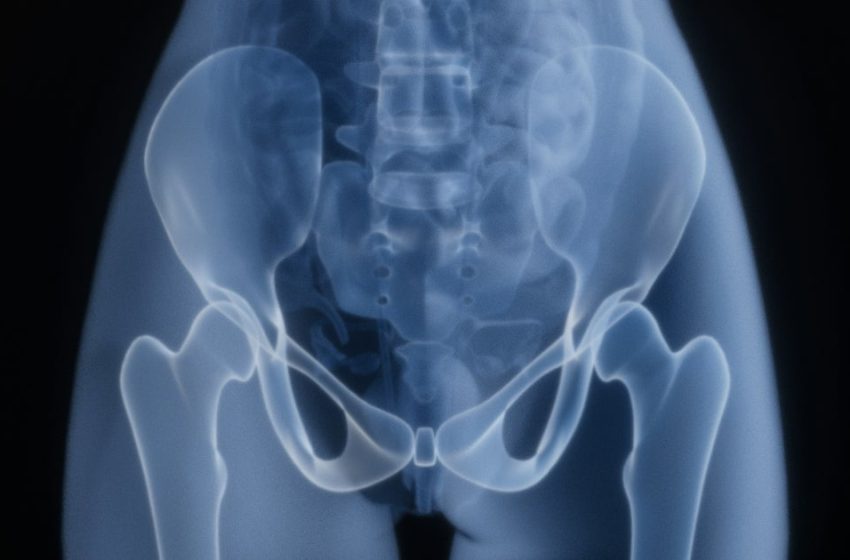

And in one study, prunes, which are high in anti-inflammatory polyphenols and calcium-balancing vitamin K, appeared to preserve bone density and strength at weight-bearing parts of the hip for post-menopausal women.

The researchers followed a group of 235 postmenopausal women, who are at greater risk of bone loss, over a year.

Postmenopausal women who didn’t consume any prunes saw a 1.1% bone loss in the same time period, while for those in the study, it stayed the same.